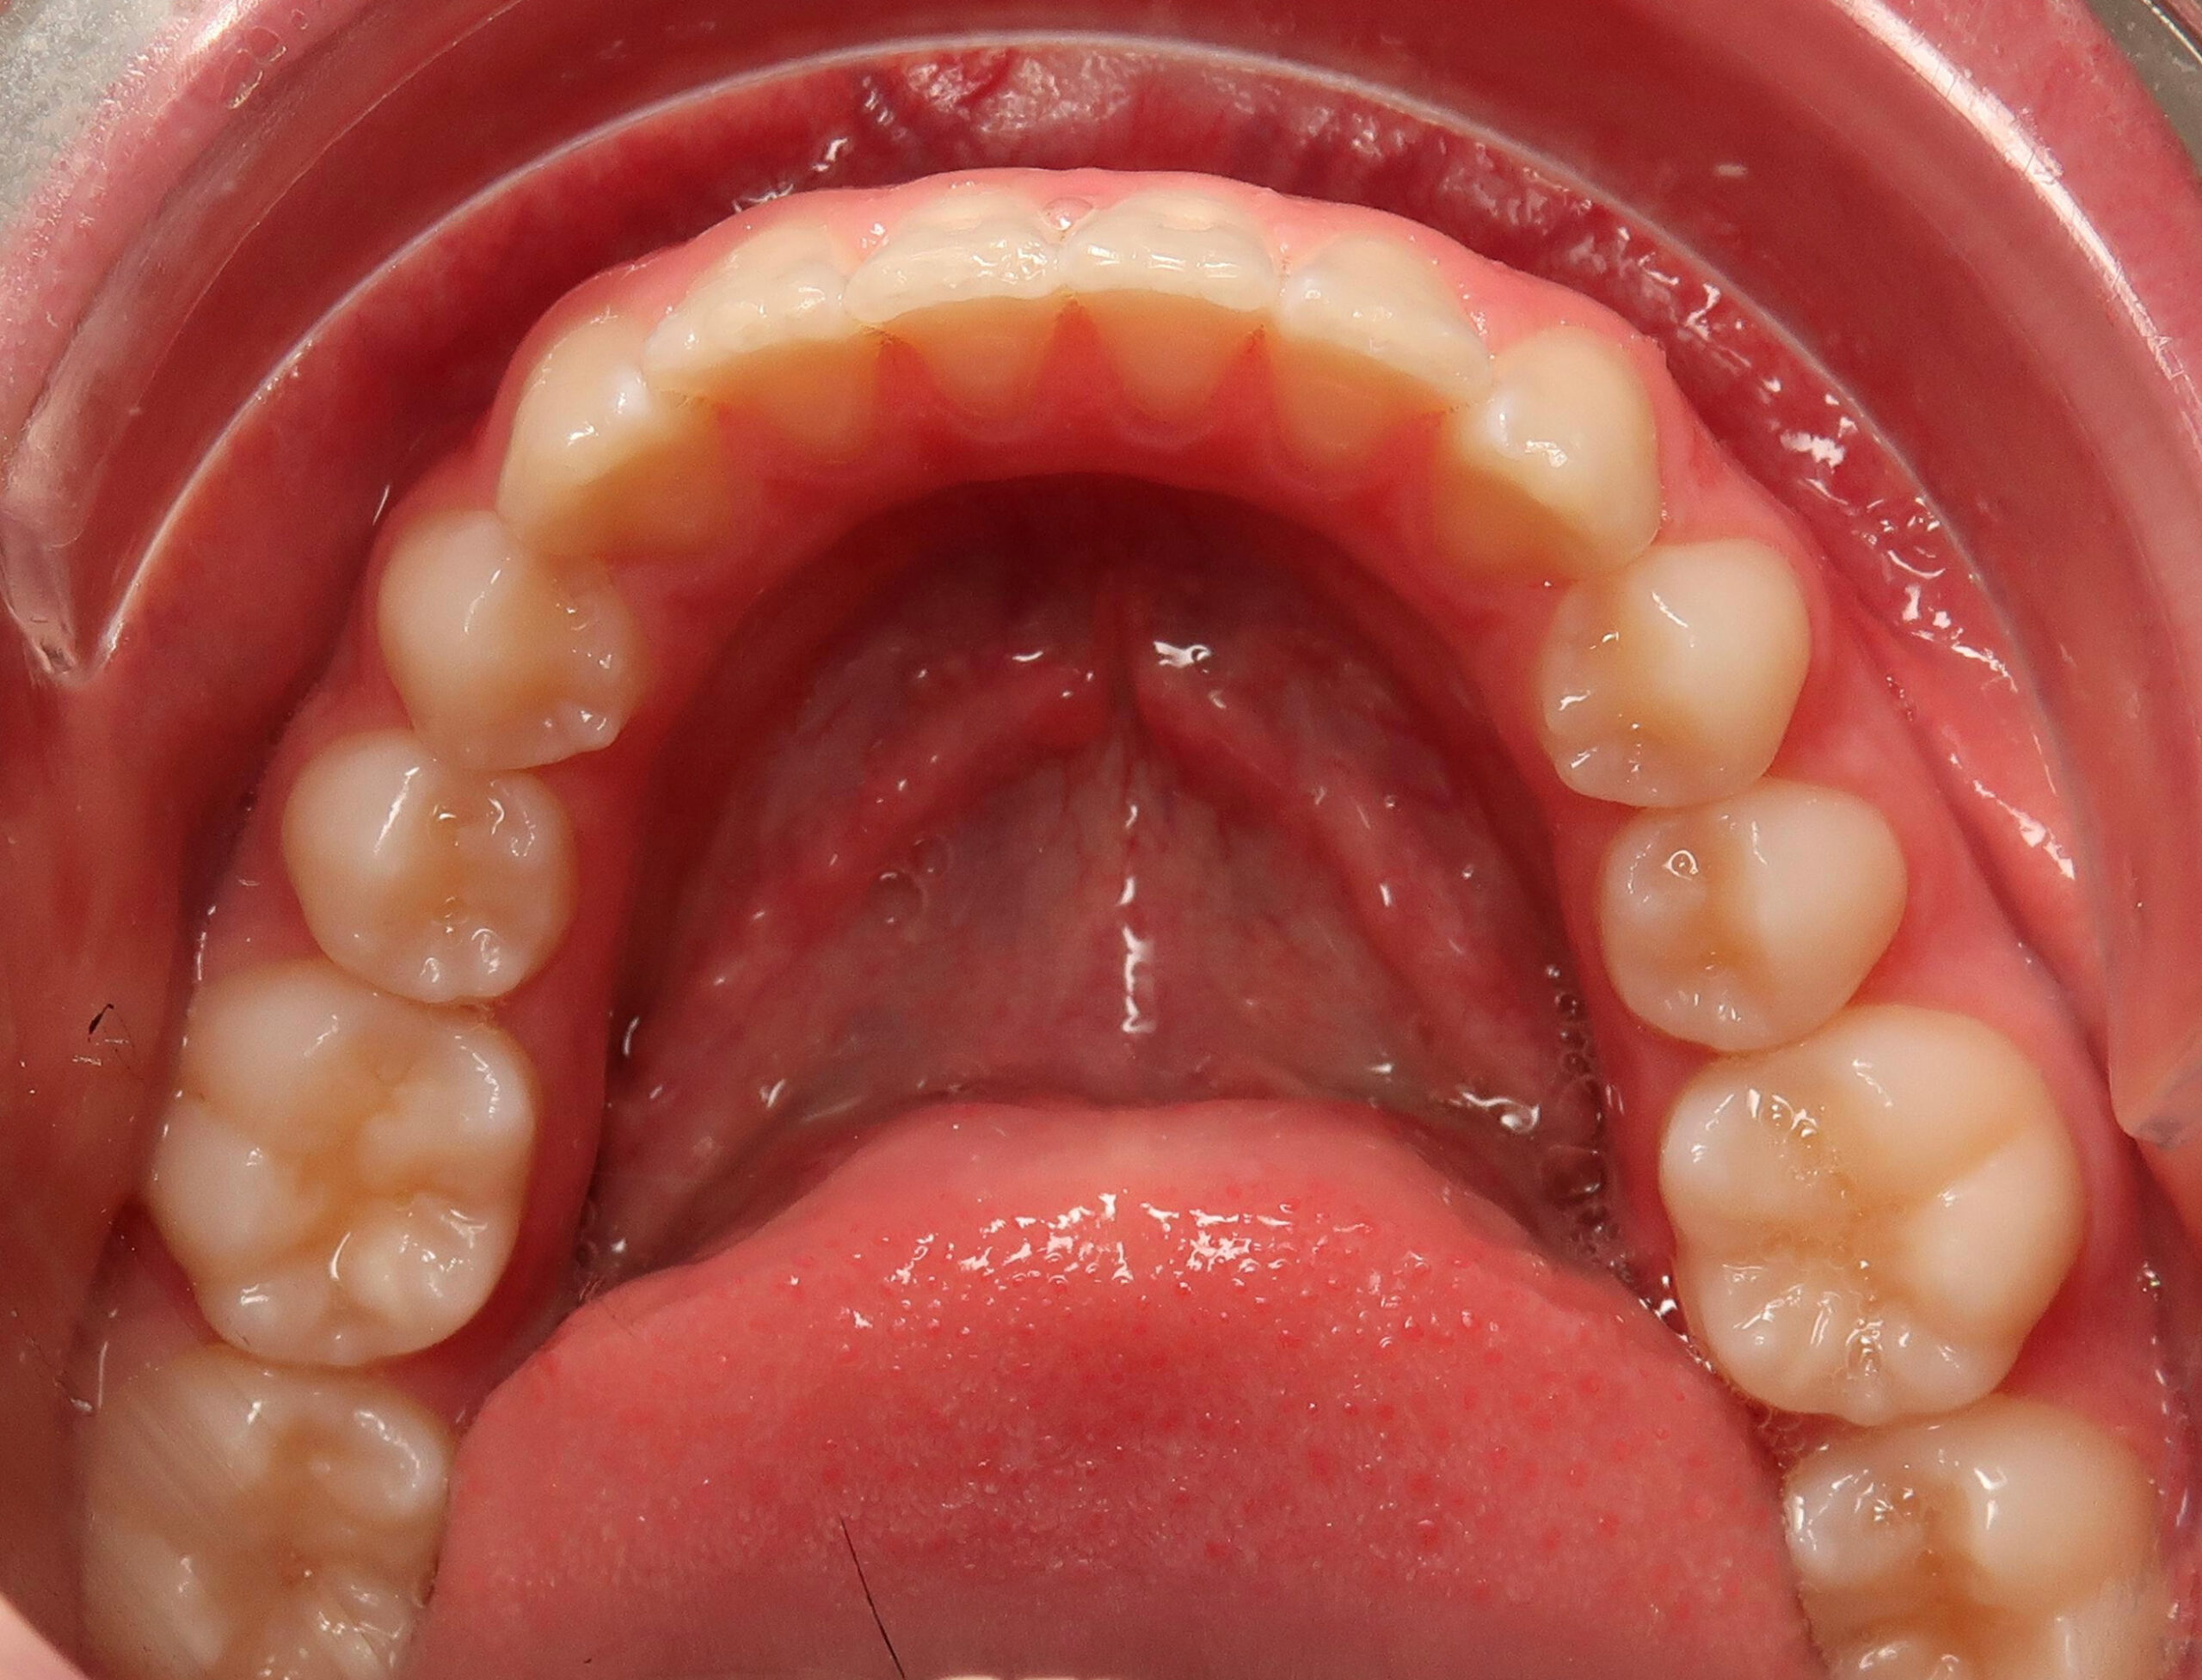

After 8 months

When reviewed after 8 months, the patient still needed distal tip of tooth 2.3, but deep bite, crowding and class II were corrected. The archform achieved after this period was the one planned: parabolic Damon archform with constriction of second molars and derotation of first molars.

At 10 months

At 10 months after start of treatment a refinement was requested with movements to correct the canine torque and tip while the patient kept using elastics allowing for the overcorrection of deepbite induced by the overcorrection of Class I and elastics mechanics.

The right timing for the treatment along with the effective and predictable aligner protocols led to achieving all objectives in less than a year proving aligners being a promising alternative to conventional appliances.